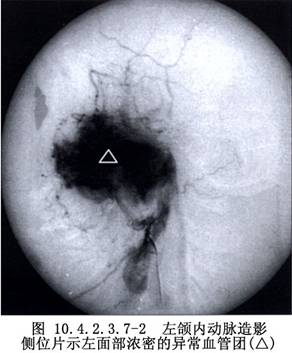

2.高血流性血管畸形,如来源于颈外动脉系的蔓状血管瘤,先天性或创伤性动静脉瘘(图10.4.2.3.7-1,10.4.2.3.7-2)。